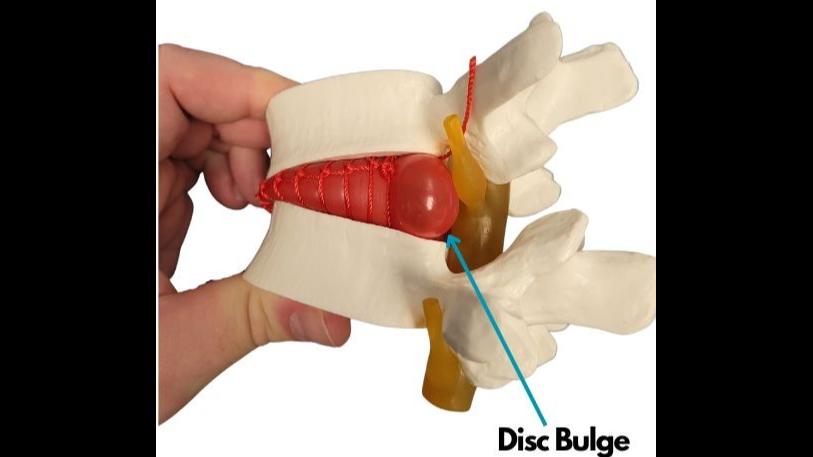

Thereporthastwokeyaims,writtenmostlyto berelevanttoanyonesufferingwithabulging disc,herniateddisc,ruptureddisc,or degenerativediscdisease,thoughitwillalso proveveryusefulandinformativetomany others,andanyonedealingwiththetopicof spinaldiscconditionsitself,